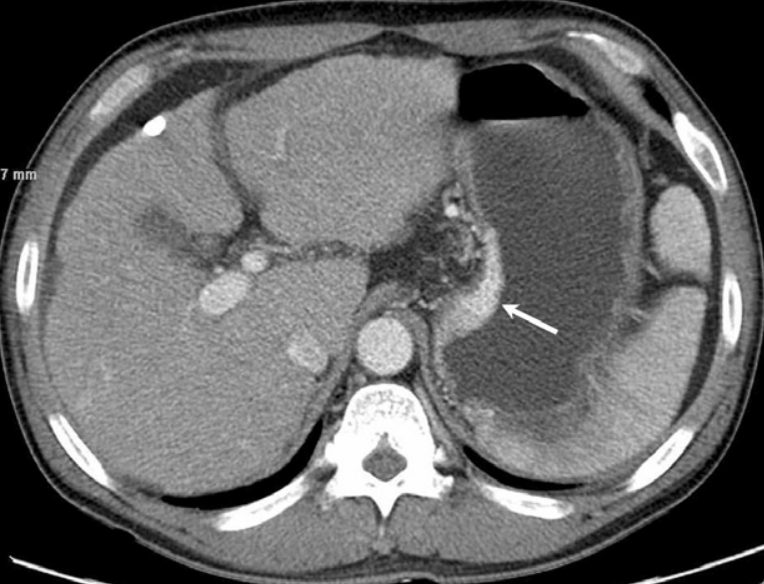

Fig. 6

Splenoportal venogram obtained immediately after glue embolization shows complete obli teration of the gastric varices and their inflow veins.